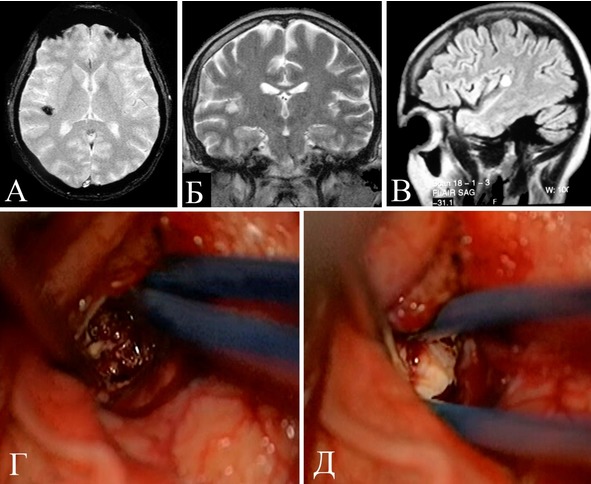

Начало заболевания за 2 месяца до госпитализации в виде тонических судорог в правой ноге. В течение последующих двух месяцев около 20 подобных приступов. Противосудорожной терапии не получал. При ЭЭГ выявлена диффузная эпилептоидная активность с акцентом слева. При МРТ выявлена кавернома в области центральных извилин слева с признаками кровоизлияния (рисунок 27).

Рисунок 27. Клиническое наблюдение №4, МРТ больного Д с каверномой в области центральных извилин слева. А – Т2 режим аксиальная проекция, Б – Т1 режим сагиттальная проекция, В – Т1 режим фронтальная проекция.

Больному выполнено удаление каверномы области постцентральной извилины слева. Во время операции при прямой стимуляции коры выявлены зоны «ноги» и «руки». Доступ согласован с полученными данными. Выполнена частичная резекция измененного кровоизлияниями мозгового вещества: резекция зоны глиотической трансформации вблизи от зоны ноги не проводилась (рисунок 28).

Рисунок 28. Клиническое наблюдение №4. Интраоперационные фотографии. Удаление каверномы области центральных извилин и использованием методики стимуляции моторной коры. А – Картирование двигательных зон. Желтым контуром указана область постгеморрагического изменения оболочек и поверхностной коры. Синим контуром указана выявленная зона «ноги». Зеленая стрелка указывает на зону руки. Красная линия – планируемая энцефалотомия вдоль центральной вены. Б – выделение каверномы. В – полость после удаления каверномы. Стрелкой показано не резецированное в процессе операции измененное мозговое вещество.

В послеоперационном периоде не наблюдалось нарастания неврологической симптоматики. Больной выписан на восьмой день после операции, рекомендован постоянный прием антиконвульсантов.

При катамнестическом осмотре спустя 3 года неврологической симптоматики так же не выявлено. Больного беспокоят редкие парциальные приступы в виде тонических приступов в правой ноге. При МРТ данные за полное иссечение каверномы (рисунок 29). Рекомендован дальнейший постоянный прием антиконвульсантов.

Рисунок 29. Клиническое наблюдение №4. Контрольное МРТ. Стрелками указана небольшая послеоперационная киста. А – Т1 режим, аксиальная проекция, Б – Т2 режим, аксиальная проекция, В – Т1 режим, фронтальная проекция. Наблюдение приведено для демонстрации метода оценки прямой стимуляции моторной коры и пирамидных трактов.